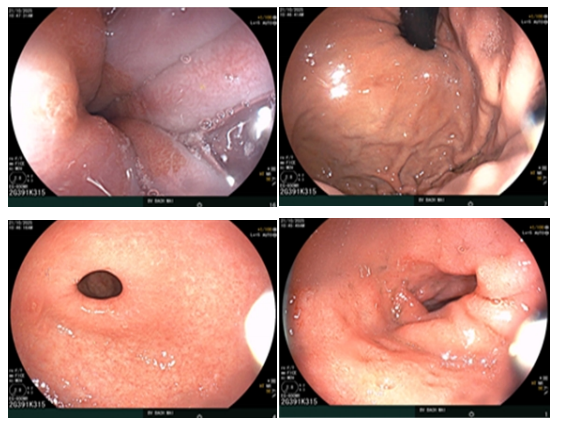

– Nội soi tiêu hóa:Viêm dạ dày- viêm hành tá tràng.

Hình ảnh nội soi thực quản dạ dày- Hành tá tràng